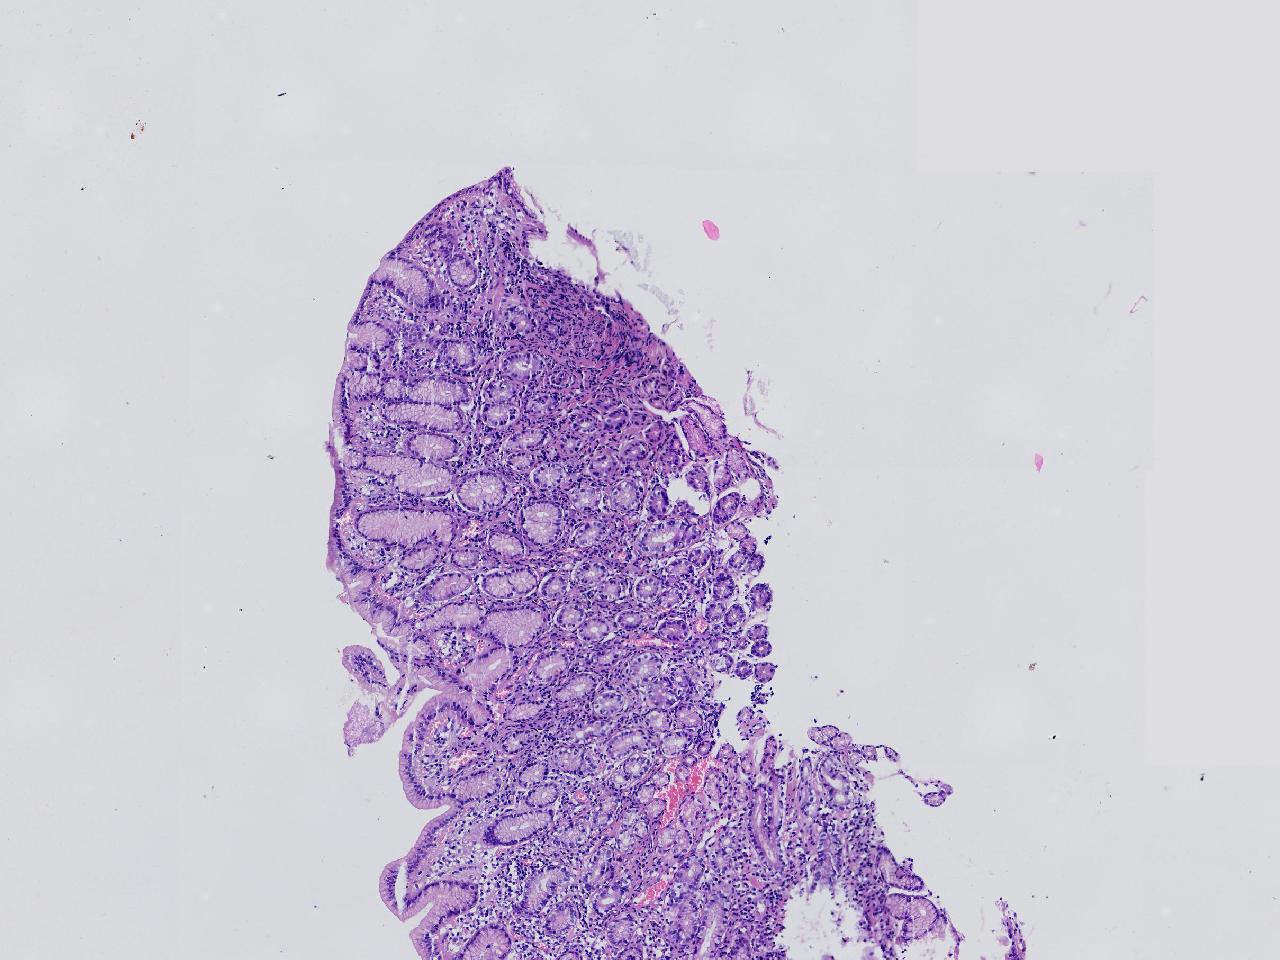

间质内是炎细胞吗?

男,49岁,胃镜活检,胃窦粘膜红白相间,以红为主,后壁见一直径约0.4cm大小片平隆起,表面糜烂,活检1块送检,质软弹性可。

胃窦活检

灰白色不整形软组织1块,直径0.2厘米。

幽门型粘膜中度慢性炎

是的,主要是淋巴细胞和浆细胞。